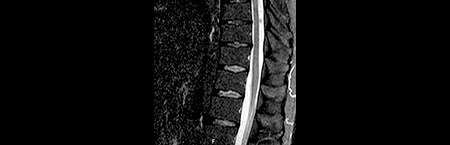

• Ressonância magnética de rebaselining 6m após início de terapêutica

Ressonância magnética

• Apresentava estabilidade da carga lesional supratentorial, e ausência de lesões captantes

• Referência a nova lesão em D6